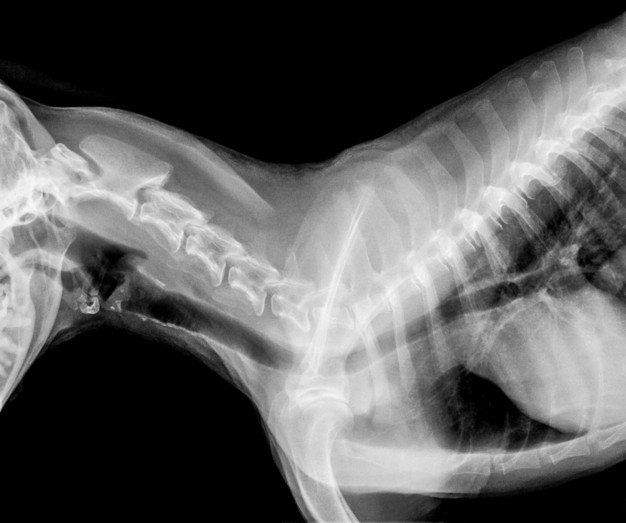

- Radiografías